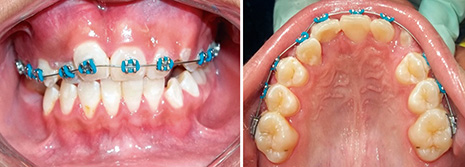

Se instruyó al paciente a realizar lavados periódicos de la cavidad tres veces al día con gluconato de clorhexidina diluida en agua (relación 1:1) por un periodo de tres meses, durante los cuales se evidenció una disminución gradual del tamaño de la lesión. A los nueve meses se observó una regeneración del defecto óseo, por lo cual se inició el tratamiento ortodóntico y se obtuvieron resultados aceptables sin evidencia de recurrencia en un seguimiento a dos años (figura 4).

Figura 4. Vista intrabucal a dos años de seguimiento incluyendo tratamiento ortodóntico, se observa mejoría en oclusión del incisivo lateral.